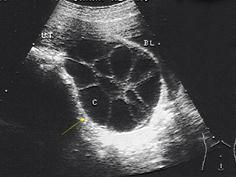

问题 女性,38岁,停经3月余,阴道不规则出血20余天。血HCG1280μg/ml,附件区超声图像见图,最可能的诊断是 ( )

选项 A、粘液性囊腺瘤 B、巧克力囊肿 C、黄素囊肿 D、浆液性囊腺瘤 E、黄体囊肿

答案 C